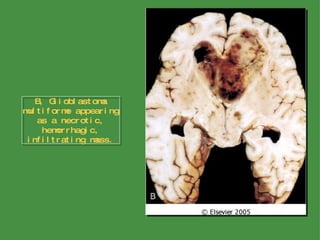

Gliomas Astrocytoma Fibrillary (Diffuse) Astrocytomas and Glioblastomas The cut surface of the tumor is either firm or soft and gelatinous; cystic degeneration may be seen In glioblastoma, variation in the gross appearance of the tumor from region to region is characteristic Morphology

B, Glioblastoma multiforme appearing as a necrotic, hemorrhagic, infiltrating mass.